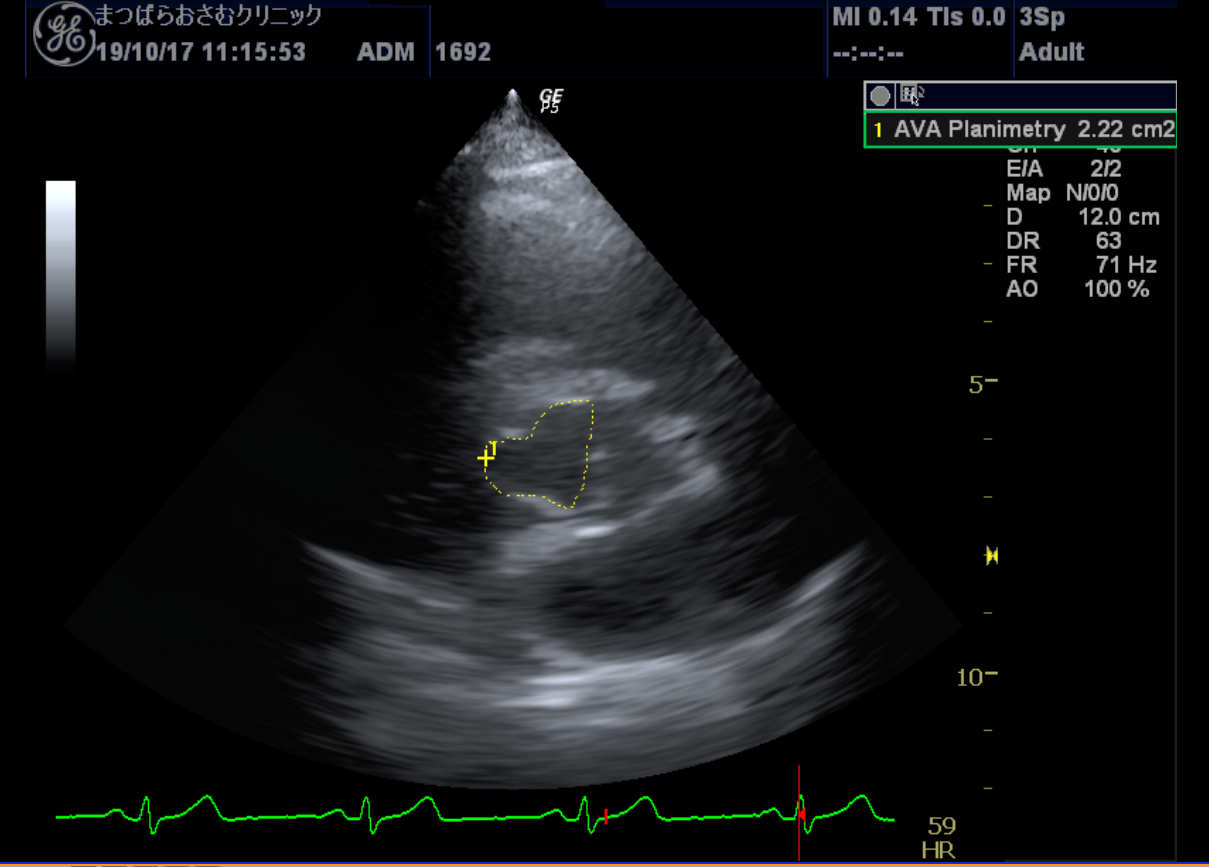

心エコー 心臓の動きや構造を観察する検査です。

胸にプローブ(探触子)を当てるだけで、心臓の大きさ、動き、弁の状態、血流の様子などをリアルタイムで確認できます。